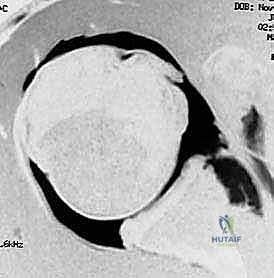

- التصوير بالرنين المغناطيسي (MRI / MR Arthrogram): المعيار الذهبي لتشخيص الأنسجة الرخوة. يوضح هذا التصوير بدقة متناهية حجم تمزق الشفا الحقاني (آفة بانكارت)، حالة الأربطة، ودرجة ترهل محفظة المفصل.

بعد تخدير المريض، يقوم البروفيسور هطيف بعمل 2 إلى 3 شقوق صغيرة جداً (لا تتجاوز نصف سنتيمتر) حول الكتف. يتم إدخال كاميرا دقيقة (المنظار) وأدوات جراحية متخصصة. تتيح الكاميرا رؤية المفصل من الداخل بوضوح فائق لتقييم حجم التمزق في الشفا الحقاني (آفة بانكارت) ودرجة ترهل المحفظة.